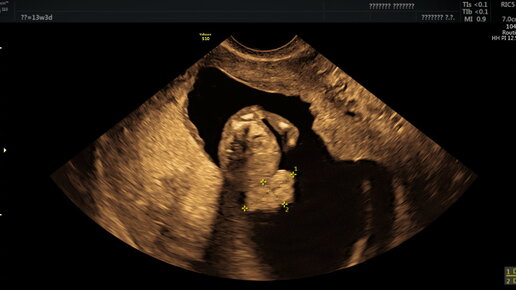

Гастрошизис